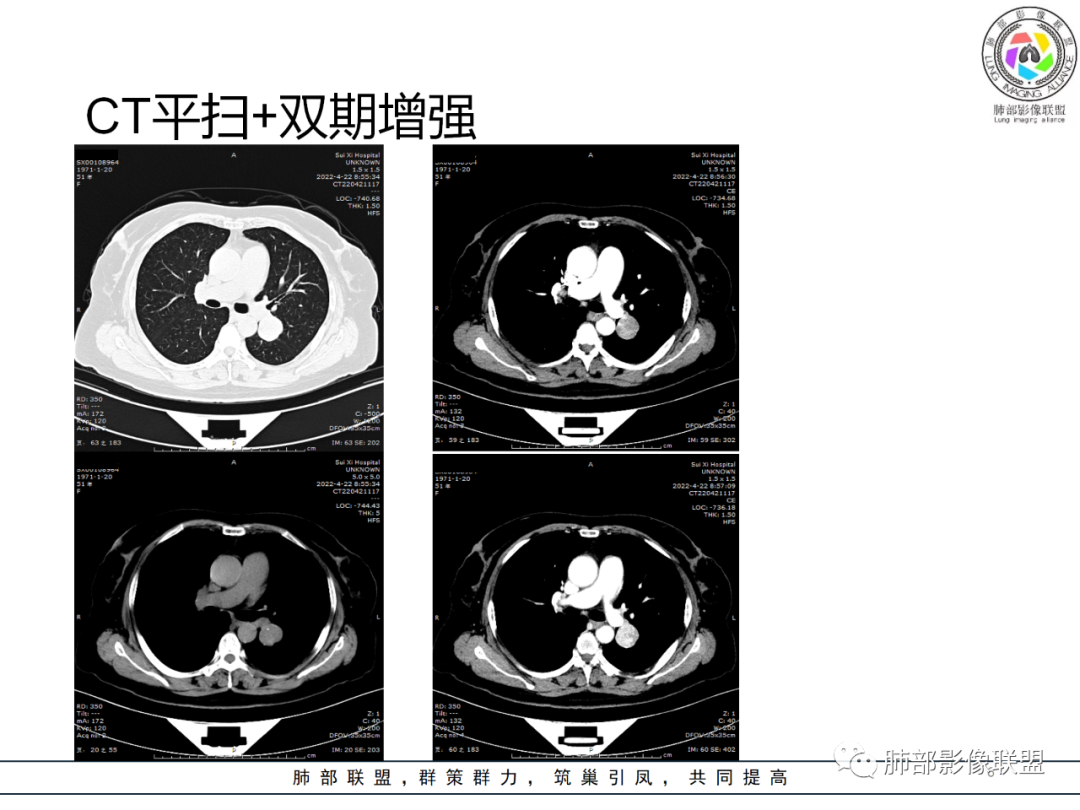

影像资料

女性51岁,右肺下叶近肺门见结节灶,内部可见钙化灶,增强呈持续性强化,首先会考虑CD,鉴别PSP、副节瘤、类癌。

患者: 女 51岁,体检发现肺部肿块3天。左侧肺门旁类圆形结节影,内部见斑点状钙化灶,增强不均匀明显强化,见血管贴边征。尾征,周围肺气肿征。

左肺门区类圆形结节,边界清晰光整,跨叶裂,其内点状钙化,明显不均匀持续强化,血管贴边,考虑PSP,鉴别血管瘤,神经内分泌癌

左肺门下方类圆形肿块,边界清楚,非常光滑,跨叶间裂内侧分布,实质内多方小砂粒状钙化,膨胀性特点,血管贴边,肺动脉分支进入供血,增强富强化,良性肺肿瘤,Sft,与肺硬化细胞瘤鉴别!

左肺门一类圆形结节影,边界清楚、光滑,局部血管束受压推移,支气管堵塞不明显,平扫密度欠均匀,可见点状钙化影,增强扫描不均匀富血供强化,内部可见低密度坏死,女性,51岁,体检发现,考虑类癌,PEComa瘤

左下肺门侧软组织包块,明显渐进性强化,似有肺动脉分支进入、增粗,边缘肺组织见空泡气肿样改变。定位肺外诊断SFT,肺内诊断psp。需要薄层

左肺占位病变,边缘光滑,内散在钙化,强化明显,边缘见血管影,考虑SFT。